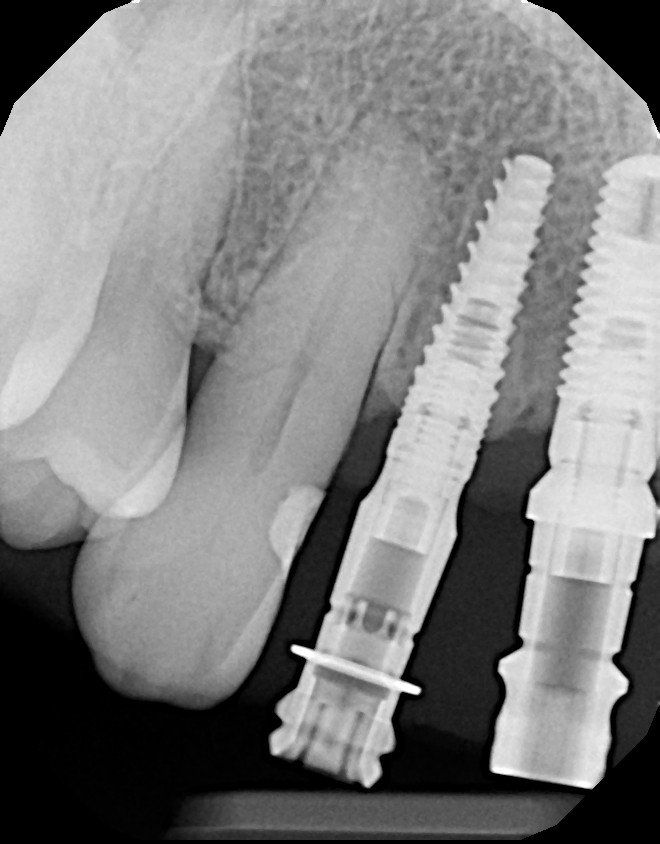

Depending on the situation, your periodontist may recommend that a dental implant be placed to replace each missing tooth. This allows the teeth to function naturally as individual units, or be connected together for increased strength. Our treatment plans are always customized to your specific needs and are based on a number of factors including your jaw strength, bite, number of missing teeth, and bone quality, to name a few.

Sometimes, an implant to replace every missing tooth is not needed or even possible. In these situations, an implant supported bridge may be recommended. An implant supported bridge is a structure similar to a traditional dental bridge, with the exception that it is supported by implants rather than natural teeth. It is generally accepted that two implants can hold a three tooth bridge, three implants can hold a four or five tooth bridge and four to eight implants are required to hold longer bridges or full-arch bridges.